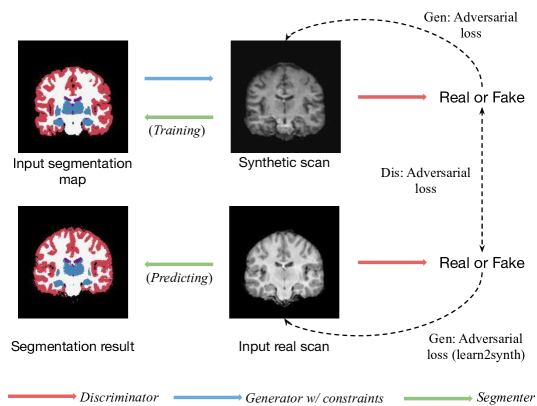

Instead, we introduce Learn2Synth, a model trained with a single objective: improving the real world accuracy of a network trained on synthetic data (Figure 1). To do so, we proceed in two steps: (1) we freeze the synthesis network, push synthetic data through the segmentation network and update it; (2) we freeze the segmentation network, push real data through the segmentation network, and update the synthesis network. Naively, if a network is fed real data, no gradients flow back to the synthesis network; the key to our approach is to leverage hyper-gradients [53, 4, 25, 11], obtained by differentiating through step (1). In summary:

We have designed a training procedure in which synthetic training examples generated using ad hoc rules are enhanced by a trainable network, before being used to train a segmentation network. The segmentation network is trained only on synthetic examples, whereas the enhancement network is trained by backpropagating a loss computed only on real images (Figure 1). This strategy encourages the augmentation network to produce samples that improve the accuracy of the segmentation network on real data; leveraging real labeled examples without directly using them in training the segmentation network. In the following sections, and represent real and synthetic labeled examples, respectively, while and denote the augmentation and segmentation functions with corresponding weights and . Our method consists of a synthetic pass and a real pass, which we describe in detail.

Here, we explore the potential of unpaired segmentation using Learn2Synth in combination with a Generative Adversarial Network (GAN). As illustrated in Figure 5, we use a GAN to generate a synthetic MRI scan that is constrained to an input segmentation map. Unlike conventional GANs, the adversarial loss on the generator is applied not only to the synthetic scan but also to the real scan. Specifically, the generator is trained to fool the discriminator by making the fake data appear more realistic, while simultaneously making the real data appear faker, through the Learn2Synth hypergradient back-propagation. The input segmentation maps and real scans are independent of each other, meaning that paired segmentation-label data is not required.